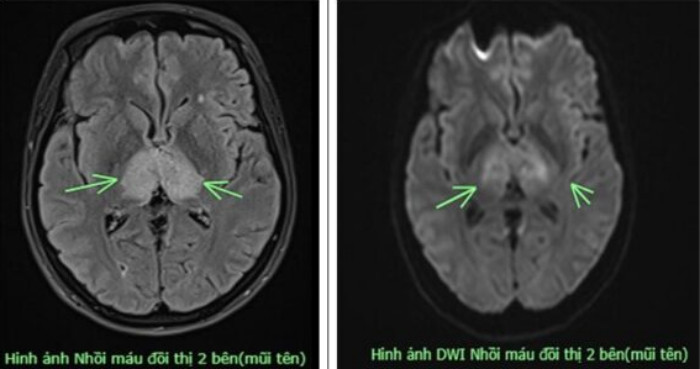

Người phụ nữ được các bác sĩ chỉ định chụp MRI, kết quả có hình ảnh nhồi máu não tại vị trí đồi thị 2 bên. Các bác sĩ hội chẩn và đặt ra nghi vấn về một bệnh lý khá hiếm gặp, bệnh lý huyết khối tĩnh mạch não. Người bệnh được chỉ định chụp MRI sọ não, xét nghiệm máu đông. Kết quả xác định đây là trường hợp huyết khối tĩnh mạch não.

Hình ảnh nhồi máu đội thị 2 bên. (Ảnh: BVCC)